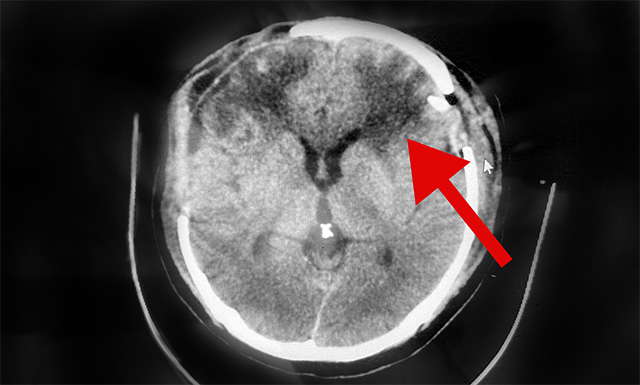

10月4日,經與神經外科6A病區(qū)侯增欣主任會診后認為,患者趙先生右側硬腦膜下血腫雖已清除,但CT檢查顯示其左側硬腦膜下仍存在較大面積血腫,顱內壓高,非常危險隨時形成腦疝,必須馬上手術。

▲術后CT示:患者左側腦內血腫已清除